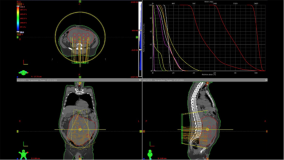

The Human Heath Campus is designed to serve as an informative resource for health professionals, working in Nuclear Medicine, Radiation Oncology, Medical Physics and Nutrition, providing insight into different aspects of modern clinical practice.

ROVER